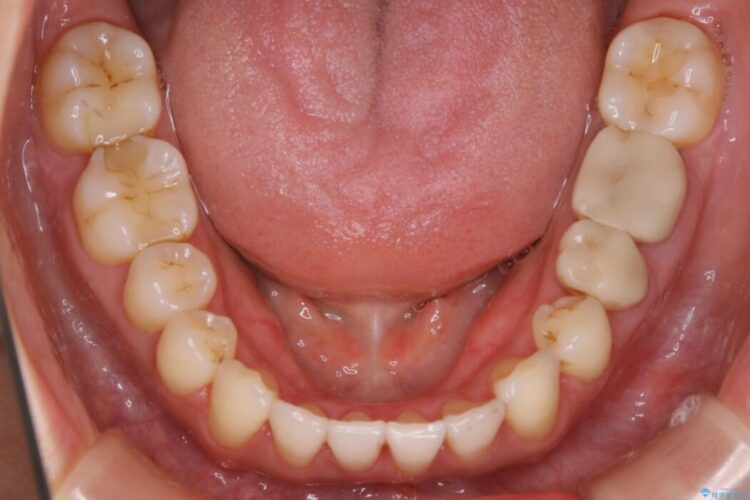

笑った時の歯の見え方が改善され患者様にご満足いただけました。

検査したところ歯の叢生自体は歯列幅の拡大やディスキング(IPR)で解決できる範囲内でした。

ですが、上顎左側の歯が前方へ寄っている状態であるため噛み合わせにズレが生じていました。

よって噛み合わせのズレをマイクロインプラントを使用して歯を移動させ、インビザラインにて歯列の整えを行うこととしました。